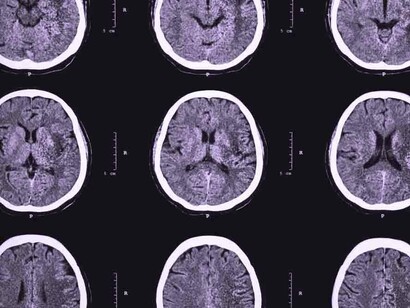

Se está observando la presencia de ictus o accidentes cerebrovasculares (ACV) en adultos jóvenes (menores de 50 años) sin factores de riesgo cardiovascular que sufren COVID-19. Es decir, personas sin la edad ni los factores de riesgo suficientes como para esperar un ictus. Se especula si realmente hay un aumento significativo, pues aún se han descrito pocos casos, o si realmente la infección favorece el desarrollo de estos.

En un artículo publicado en The Lancet del pasado mes de abril, se trata el tema de por qué los accidentes cerebrovasculares están ocurriendo en jóvenes aparentemente sanos. En dicho artículo, investigadores del Hospital Universitario de Zúrich notaron que el virus SARS-CoV-2 (COVID-19) infecta a los huéspedes a través de la enzima convertidora de angiotensina (ACE2), expresado no solo en los pulmones sino también en el corazón, riñón, intestino y células endoteliales. Y describieron tres casos en los que observaron infección viral directa de las células e inflamación endotelial difusa (endotelitis). La endotelitis por COVID-19 podría explicar la función microcirculatoria deteriorada en diferentes lechos vasculares y sus secuelas clínicas en pacientes con COVID-19.

Investigadores holandeses describieron otro posible mecanismo detrás del aparente aumento del riesgo de accidente cerebrovascular en un artículo publicado en línea, en abril, en la revista Thrombosis Research. En 184 pacientes de la UCI con neumonía comprobada por COVID-19, se observó un resultado de embolia pulmonar aguda sintomática, trombosis venosa profunda, accidente cerebrovascular isquémico, infarto de miocardio o embolia arterial sistémica en un 31%, una cifra que llamaron «notablemente» alta. Se especula un problema con el sistema de coagulación o con el revestimiento endotelial de los vasos sanguíneos.

Cualquiera que sea la causa del mayor riesgo de accidente cerebrovascular asociado con COVID-19, se ha visto que, tanto la presentación como el resultado, son a menudo peores que en otros accidentes cerebrovasculares. Por lo general, estos pacientes con COVID-19 presentan más de un vaso bloqueado con un trombo. En el estudio de una serie de casos, la mortalidad fue de alrededor del 55 por ciento. A pesar de reabrir los vasos obstruidos, terminan teniendo otro ictus importante. Su sangre sigue coagulándose con rapidez.